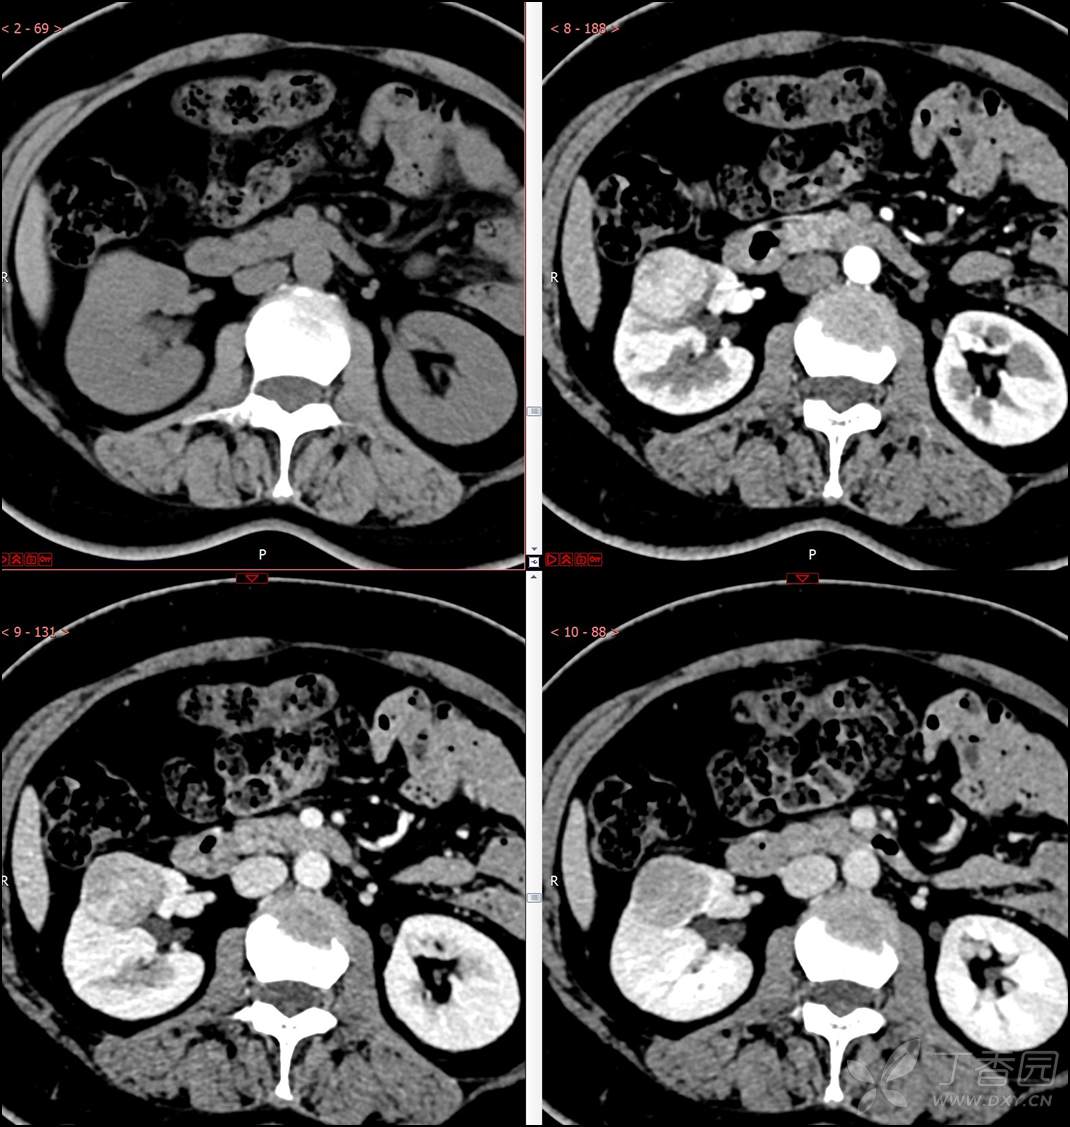

【影诊笔记516】中年女性,检查发现肾占位2周就诊~『嗜酸细胞腺瘤』

主诉:检查发现肾占位2周

简要病史:患者2周前体检发现肾实质性占位,无腰痛,无血尿,无尿频、尿急、尿痛,无发热,在外未行特殊治疗。患者为行进一步治疗就诊于我院,门诊以“肾占位性病变 ”收入我科,患者自发病以来,神志清,精神可,小便如上所述,大便正常,体重无显著变化。